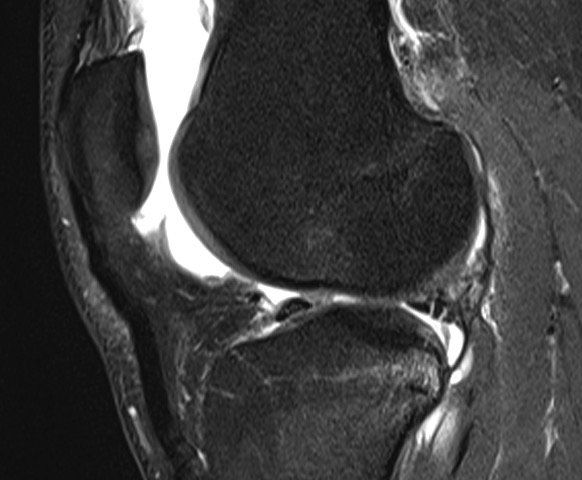

Die Arthroskopie ist eine moderne, äußerst präzise Methode, um verletzte und beschädigte Gelenke operativ zu behandeln. Über winzige Hautschnitte werden dabei eine Kamera und Spezialinstrumente in das Gelenk eingeführt, die Bilder werden auf einen Monitor übertragen. Je nach Befund erfolgt dann direkt die geeignete Therapie im Gelenk.

Die Kniearthroskopie kann ist eine minimalinvasive Operationsmethode (Schlüssellochchirurgie) und kommt vor allem in der Meniskus- und Kreuzbandchirurgie zum EinsatzMinimal invasiv - Maximal erfolgreich